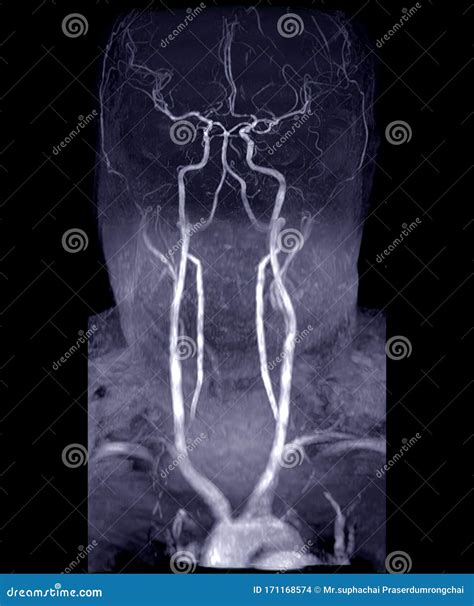

The core technology behind an MRV is the same as a standard MRI machine—a large tube surrounded by a powerful circular magnet. For an MRV, the process is often enhanced with the use of a gadolinium-based contrast agent. This contrast dye is injected into a vein in your arm, which helps the blood vessels "light up" on the resulting images, providing a clear contrast between the vessels and the surrounding brain tissue.

The imaging machine detects the signals emitted by the blood flow within these enhanced vessels, creating a high-resolution map of the venous drainage system. The entire process is non-invasive, meaning no surgical intervention is required.